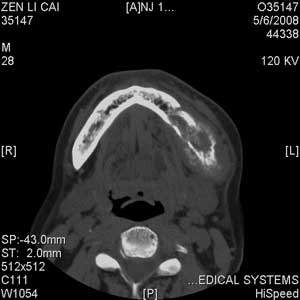

以下是引用jiangjing在2008-5-28 15:56:00的发言:[br]下颌骨左侧部骨质破坏,轻度膨胀,瘤骨形成,软组织肿胀考虑 恶性骨肿瘤-----肉瘤类